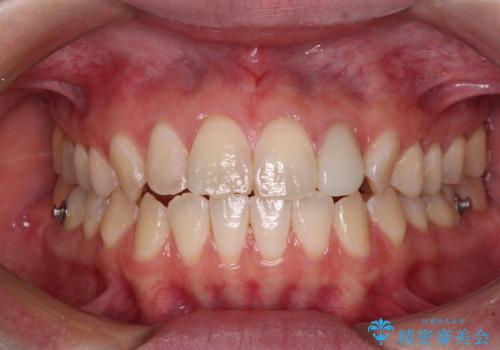

開咬を治す インビザラインによる矯正治療

- 上下前歯の開咬を気にして来院された患者様です。

開咬はインビザラインを用いると有意に改善ができるため、インビザラインによる矯正治療を行うこととしました。